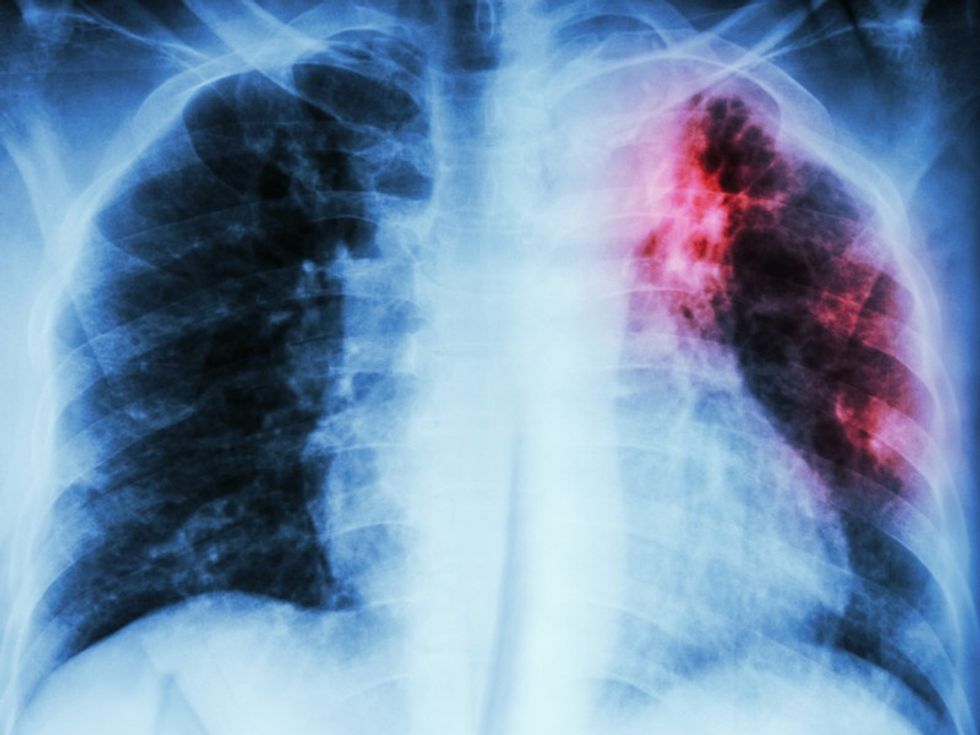

Tuberkulozi është një infeksion bakterial, i cili prek kryesisht mushkëritë, por gjithashtu mund të prekë barkun, gjëndrat, kockat dhe sistemin nervor.

Tuberkulozi, i cili prek mushkëritë, është lloji më i zakonshëm dhe më ngjitës i tuberkulozit. Megjithatë, ajo përhapet vetëm pas ekspozimit më të gjatë me dikë që ka sëmundjen. Në shumicën e njerëzve të shëndetshëm, sistemi imunitar i trupit do të luftojë kundër infeksionit dhe do të vrasë bakteret, pa shkaktuar asnjë simptomë.

Nëse sistemi juaj imunitar nuk mund të vrasë ose të përmbajë bakteret, ai mund të përhapet në mushkëri, si dhe në pjesë të tjera të trupit tuaj. Ky është tuberkuloz aktiv dhe simptomat do të fillojnë të zhvillohen brenda disa javësh ose muajsh. /Telegrafi/